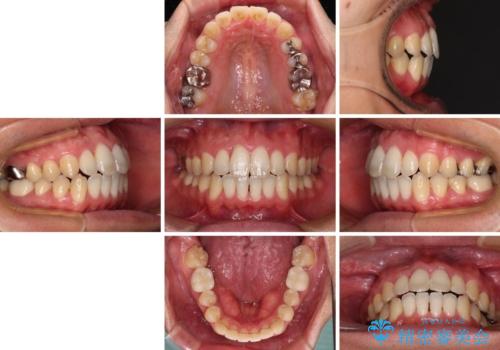

上顎歯列全体を後方に移動させたため、口元の突出感も改善され、装置を外してからは口が閉じやすくなりました。

また、上下犬歯が接触するようになったため、奥歯にストレスのかからない歯ぎしりができるようになり、顎の疲れも改善されました。